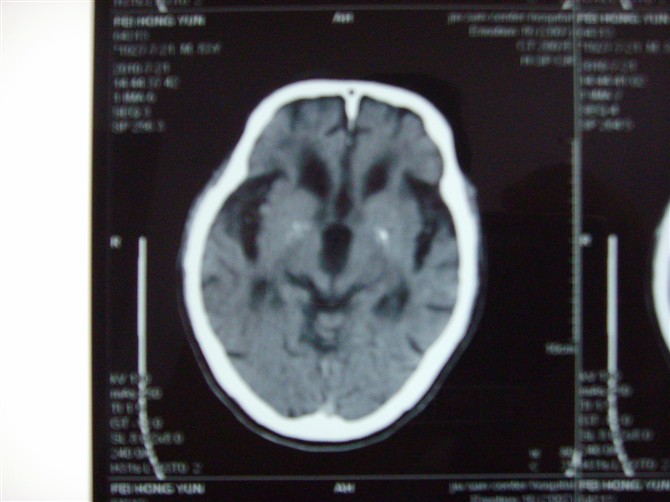

标题: CT27993:男 83岁 头晕伴双下肢无力一天 [打印本页]

标题: CT27993:男 83岁 头晕伴双下肢无力一天

脑萎缩。伴小脑齿状核、苍白球钙化。必要是mri进一步检查。

脑萎缩。伴小脑齿状核、苍白球钙化.脑白质脱髓鞘病变

脑白质变性、脑萎缩。甲状旁腺功能减退。

1)双侧小脑半球脑软化灶。2)全脑萎缩。3)脑白质病。